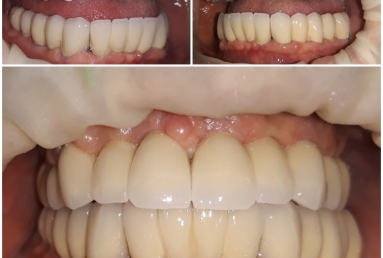

Full mouth rehabilitation with dental implants and fixed ceramic crowns

After implant healing, fixed bridges were made out of porcelain fused to metal.